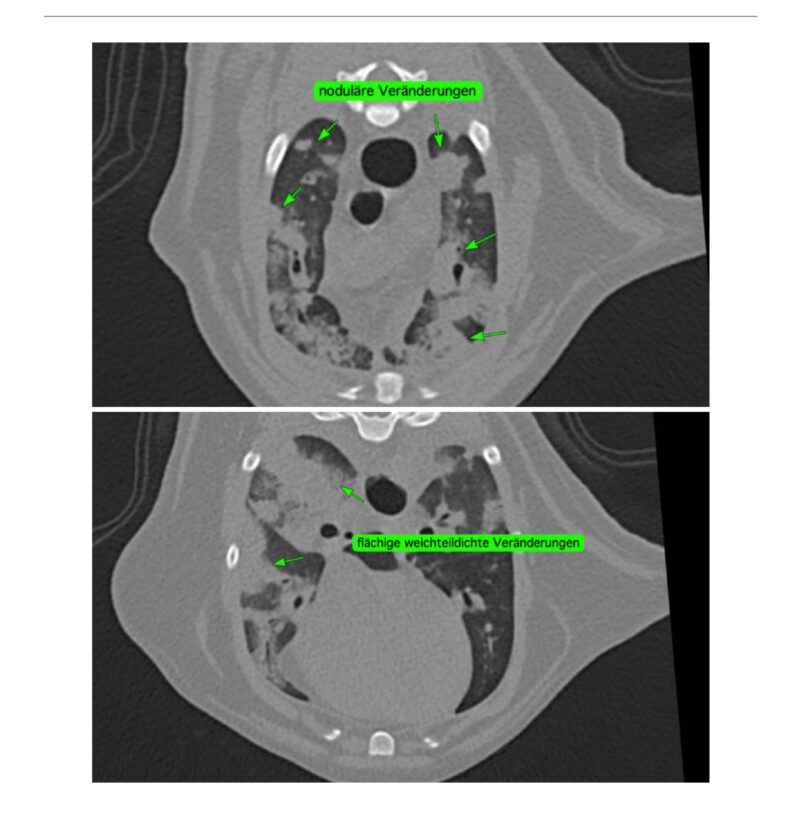

Die initiale Blutuntersuchung ergab eine Leukopenie und erhöhte Leberwerte. Diese Befunde ließen eine systemischen Infektion vermuten, wobei insbesondere eine Toxoplasmose in Betracht gezogen wurde. Ein serologischer Test auf Toxoplasma gondii wurde am selben Tag eingeleitet, um die Verdachtsdiagnose zu bestätigen. Zusätzlich wurde ein Röntgenbild des Thorax angefertigt, das eine beidseitige pulmonale Infiltration und perihiläre Verdichtungen aufzeigte. Die serologischen Resultate waren positiv und bestätigten das Vorhandensein von Antikörpern gegen Toxoplasma gondii. Im Gesamtkontext wurde daher der Verdacht auf eine Toxoplasmose erhärtet, die aufgrund der Immunsuppression der Katze und Kontakt zu potentiellen Überträgertieren begünstigt wurde.